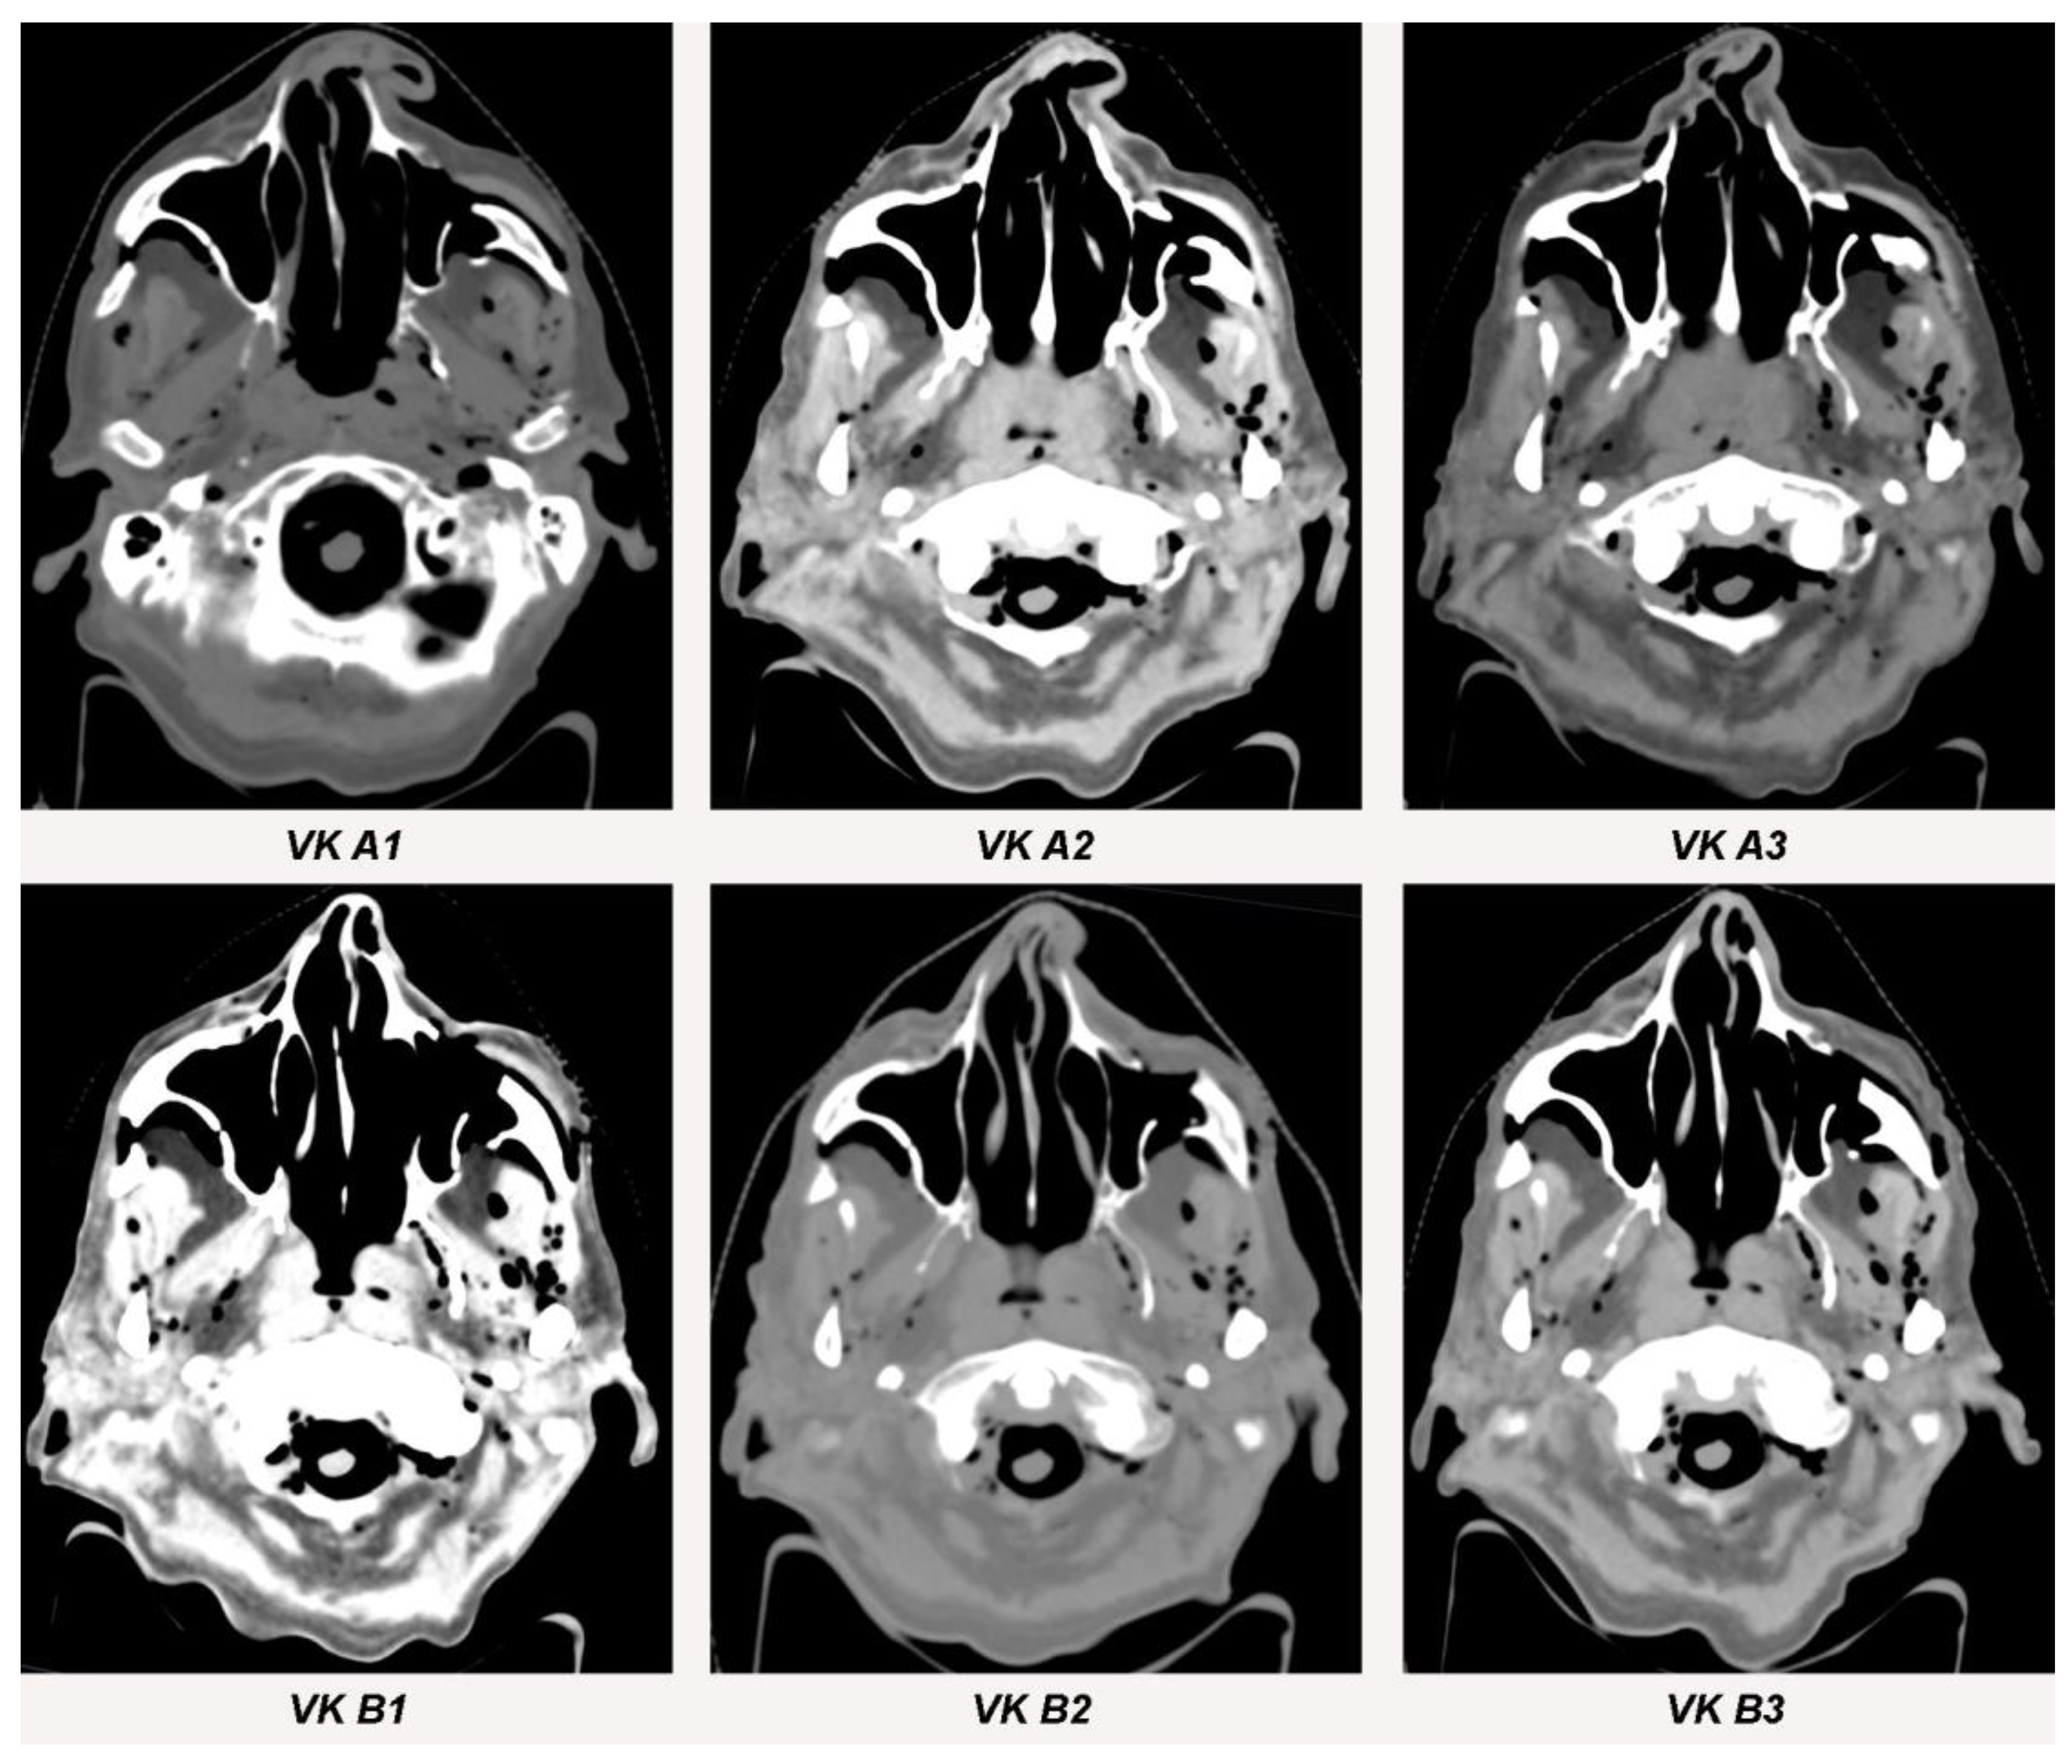

3.1. Streak Artifacts

3.1.1. Implant Material

3.1.2. Metallic Artifact Reduction Algorithm

3.2. Blooming Artifacts

3.2.1. Implant Material

3.2.2. Metallic Artifact Reduction Algorithm

3.3. Image Quality